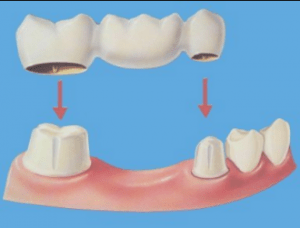

A replacement tooth is then fitted to the implant, which allows the tooth to remain in place. Basically, a dental implant provides a permanent foundation for a replacement tooth. To see also : Cap On Tooth. Although the cost varies depending on several factors, on average, the estimated cost of a single dental implant ranges from $3,000 to $6,000.